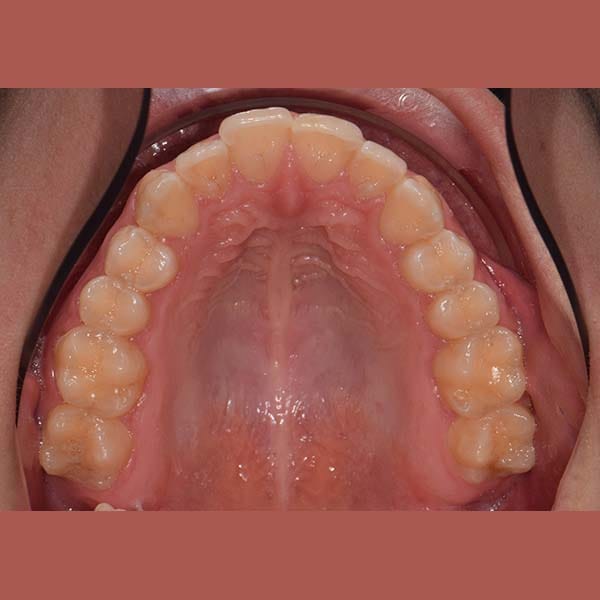

AFTER

Our young reviewer asked me to treat the simple overlay in her front upper and lower teeth, but she didn’t want anyone to notice her braces. The ideal solution was the invisible braces from Invisalign. After a few months of treatment, all of her teeth were beautifully aligned, and most importantly, no one noticed that she was wearing braces.